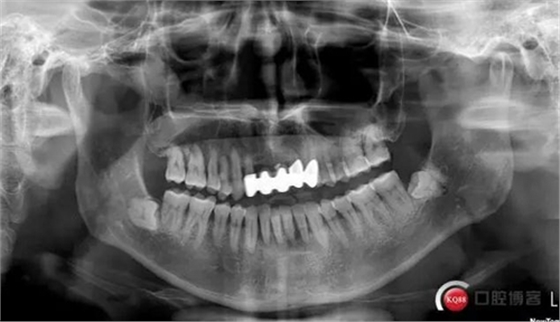

此患者為下頜前牙區(qū)松動(dòng)牙試保留案例,牙周炎伴根尖周炎,并且31頰舌雙根管。術(shù)中由于我的個(gè)人失誤,導(dǎo)致整體治療過(guò)程延長(zhǎng),特此總結(jié),自我警醒。

患者蔣某,男性,1963年出生。2017年7月4日就診。

主訴:下前牙松動(dòng)約三年

現(xiàn)病史:患者約三年前發(fā)覺(jué)下頜前牙開(kāi)始松動(dòng),伴加重,現(xiàn)影響咬合。曾于外院就診,行牙周潔治(約一年前),建議拔除下頜前牙后種植,患者拒絕。

檢查:口腔衛(wèi)生狀況欠佳,牙面可見(jiàn)大量色素附著,牙石II°,尤以下頜前牙舌側(cè)及后牙頰側(cè)為重。牙齦紅腫,BI3-4°,PD下頜前牙區(qū)4-6mm。31松動(dòng)III°,溫度測(cè)試無(wú)反應(yīng),叩不適。32、41、42松II°+,32溫度測(cè)試遲鈍,叩(-)。

X線(xiàn)示牙槽骨吸收,下頜前牙區(qū)可見(jiàn)齦下牙石影像,牙槽骨吸收至根尖1/3,根周透射影像。

診斷:慢性牙周炎

31慢性根尖周炎

32牙髓充血?慢性牙髓炎?